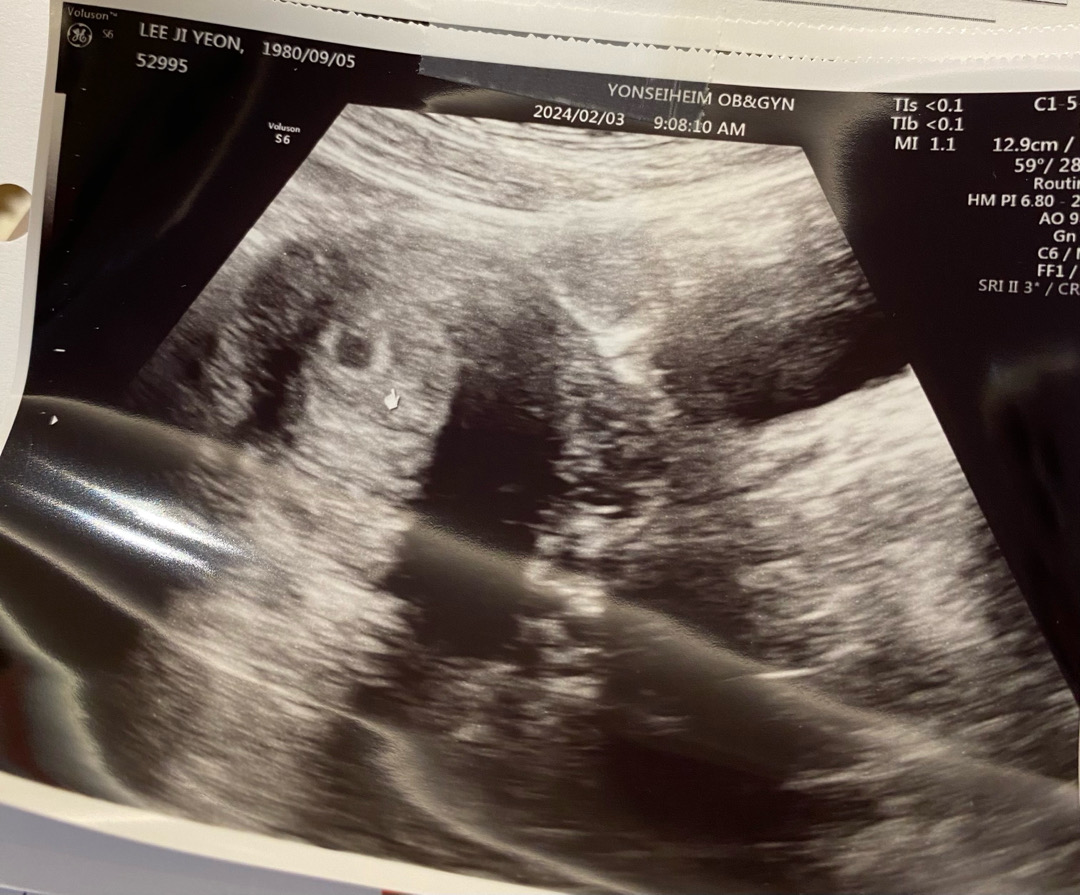

45세 첫임신

예기치 않은 임신 너무 많은 나이에 아이를 가졌어요 오늘 첫 초음파로 아기집확인하고 왔어요 확인 전엔 실감도 안나고 노산이라 걱정이 너무 많았는데 자리 잘 잡았다는 선생님 말에 안심이 되네요~아직 5주라 아기는 안보인다고 하셨는데 집이랑 난황 확인한걸로 만족합니다 10개월 무탈이 보내서 건강한 아이 맞이할수있겠죠?? 우리 같이 힘내요 ㅎㅎ